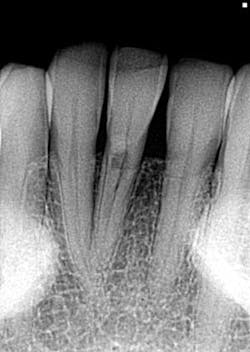

I offer the four clinical examples below to help you distinguish between internal and external resorption.- The outline of the canal in No. 24 is easily seen through the lesion, unaltered, and appearance is slightly ragged and irregular (figure 5).